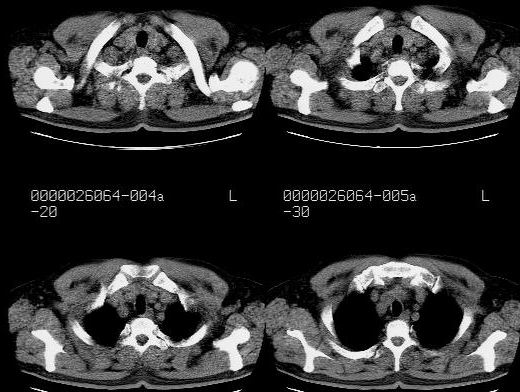

患者,男性,71岁,因咳嗽而就诊,

典型的右肺中心性肺癌并纵隔淋巴结转移

考虑右肺中心性肺癌并右肺门及纵隔淋巴结转移。